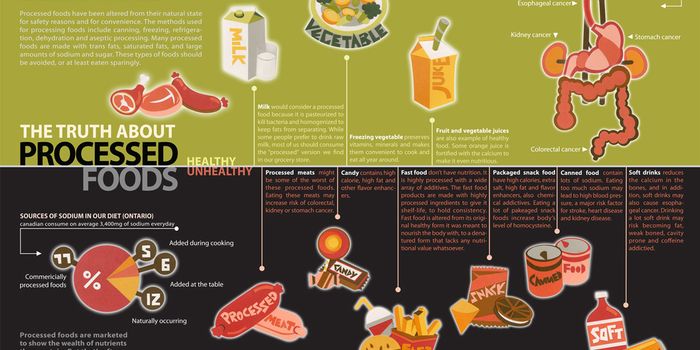

MAR 06, 2023CancerEvidence supports the interplay between diet, nutrition, and obesity and their collective influences on health and welln ...

JAN 10, 2016ImmunologyFilling up on processed foods is usually easier than planning and cooking a healthy meal, but a new study shows that tak ...